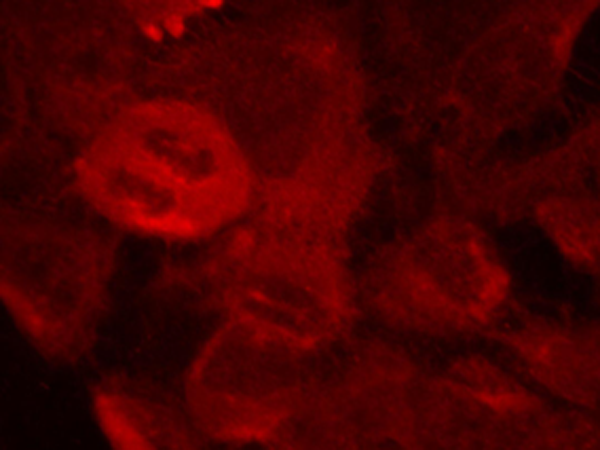

WB, IHC, IF

Positive control:

Hela cells

Recommended dilution:

100-200